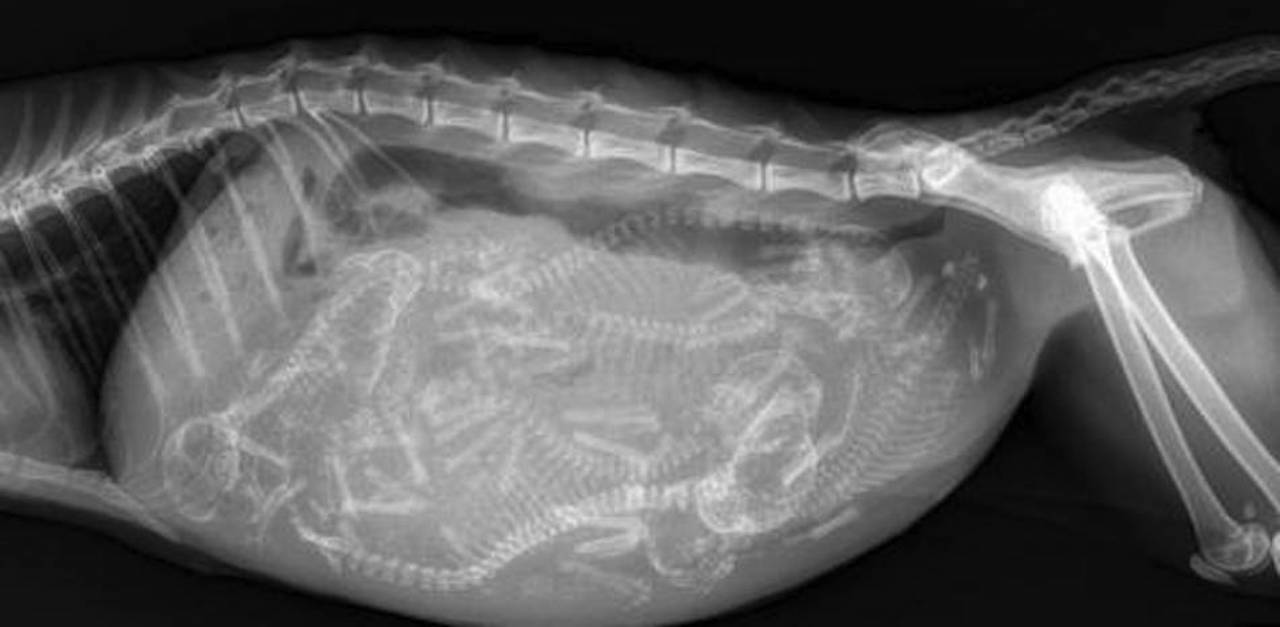

Pregnant Rabbit Xray . This can be done later in the pregnancy to get a. How early can i scan a rabbit? Confirming the pregnancy with a veterinarian is a top priority to ensure your pregnant rabbit’s proper care and support throughout her pregnancy. Rabbit pregnancy tests work by various methods such as ultrasound imaging to visualize fetal structures, hormonal assays. In the present study pregnancy. Positive confirmation of pregnancy has been documented as early as 7 days in rabbits, but only by the presence of fluid inside the.

Xray Pregnant Rabbit 31 Days Stock Photo Download Image Now Rabbit Pregnant Rabbit Xray In the present study pregnancy. This can be done later in the pregnancy to get a. Positive confirmation of pregnancy has been documented as early as 7 days in rabbits, but only by the presence of fluid inside the. Confirming the pregnancy with a veterinarian is a top priority to ensure your pregnant rabbit’s proper care and support throughout her. Pregnant Rabbit Xray.